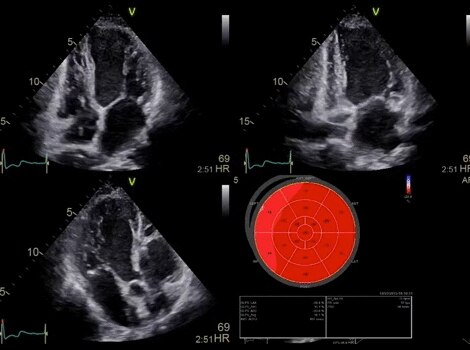

VividTM Family Cardiac Ultrasound Automated Function Imaging (AFI)

Assess left ventricular function and cardiac performance with clarity, improving clinical confidence. Read More

Vivid Family Cardiac Ultrasound

Vivid E95 with cSound performance makes 4D as easy as 2D to quantify left ventricular wall motion. Read More

Vivid™ Family Cardiac Ultrasound with Automated Quantification

Assess left ventricular function and cardiac performance with clarty,improving clinical confidence.Read More